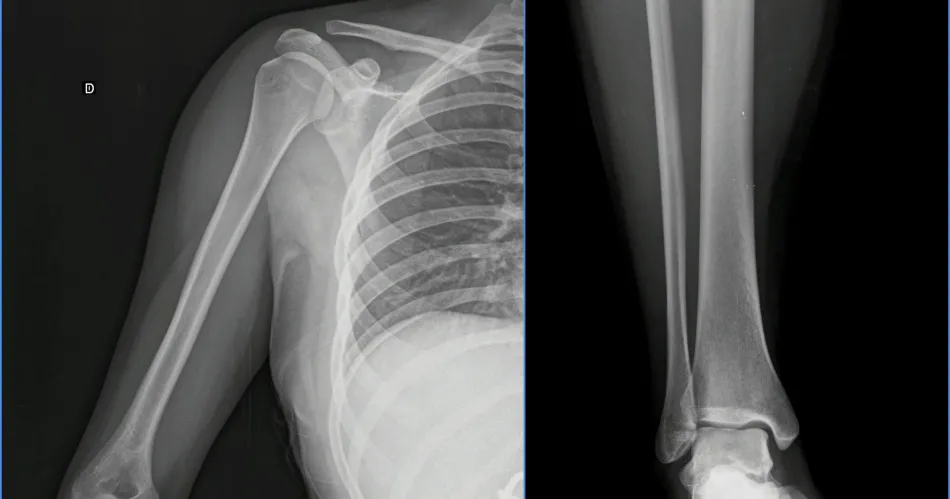

LESIONES. La damnificada fue examinada por los forenses que constataron las heridas.

Los denunciados podrían ser imputados por "Lesiones graves", ya que por la fractura del hombro, el forense diagnosticó 45 días de curaciones.

Ayer el médico forense examinó a la joven y diagnosticó 45 días de curaciones. La causa es investigada por la fiscal Silvia Jaime Luna.